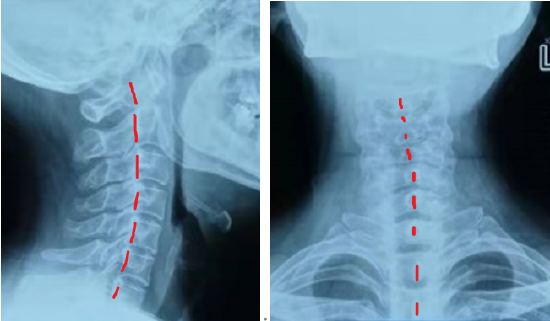

正经科普如何判断自己颈椎是否弯了

图片尺寸550x321